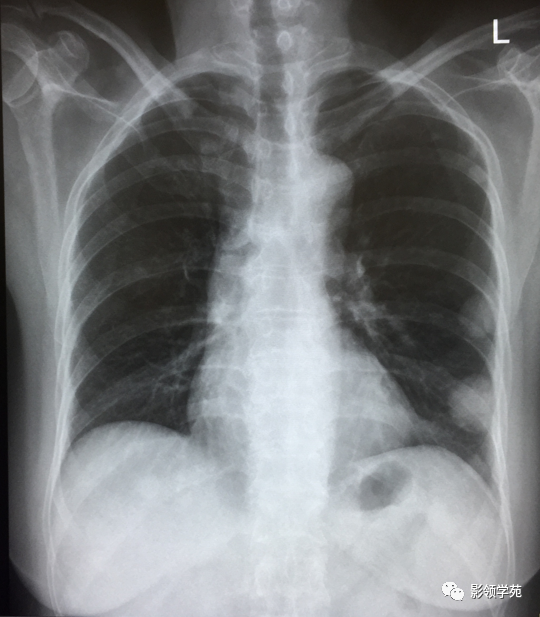

血行转移:双肺多发密度一致、大小形态不一结节状影(下图)

淋巴转移:肺门影增大,自肺门向外部规则索条状影(下图)

双肺淋巴道转移癌。胸部正位片示双侧中下肺野多发结节状及网格状高密度结节影,可见克氏B线 (下图)